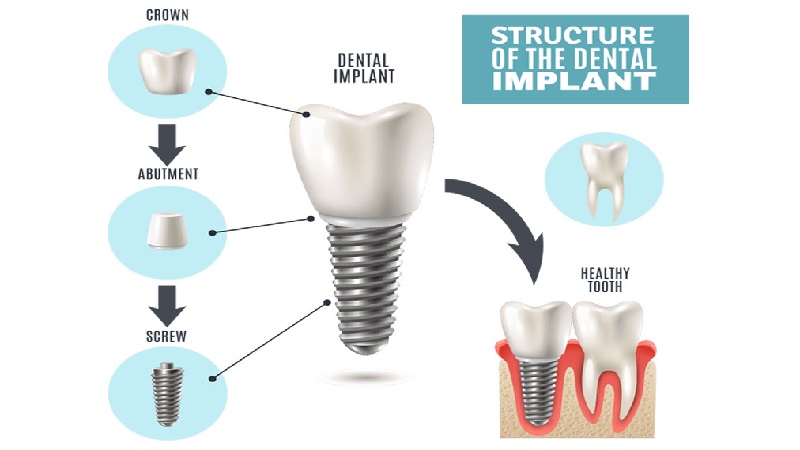

- ایمپلنت دندان اصفهان

7 نکته مهم در رابطه با کاشت دندان و ایمپلنت دندان

۷ نکته درباره ایمپلنت و کاشت دندان که باید بدانید !

امروزه با پیشرفت علم در زمینه دندان پزشکی راهکارهای مختلفی برای درمان دندانهای از دست رفته اختراع شده است که یکی از این راهکارها ایمپلنت دندان است که امروزه توسط پزشکان توصیه میشود و بهترین درمان برای دندانهای از دست رفته است. در ادامه این مطلب به نکاتی پیرامون ایمپلن دندان می پردازیم :

- نحوه کاشت ایمپلنت دندان